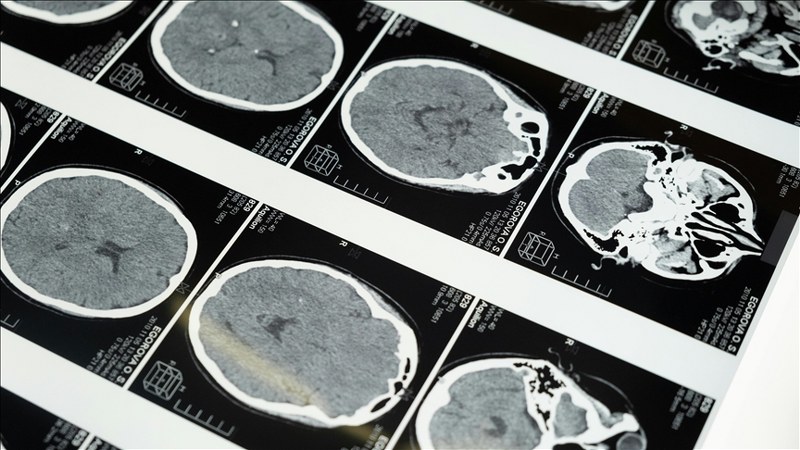

Biruni Üniversite Hastanesi Nöroloji Uzmanı Prof. Dr. Talip Asil, 29 Ekim Dünya İnme Günü kapsamında, inme ve inme semptomlarıyla ilgili uyarılarda bulundu.

Hastaneden yapılan açıklamada görüşlerine yer verilen Asil, dünyada en sık görülen üçüncü ölüm nedeni olan inmenin, yüzde ani kayma, kol veya bacakta güçsüzlük ve konuşma bozukluğu gibi belirtilerle ortaya çıkabileceğini belirtti.

Diyabet, hipertansiyon, obezite, yüksek kolesterol ve kalp hastalarının inme açısından riskli grupta olduğunu vurgulayan Asil, “Erken müdahale, felcin kalıcı hasar bırakmasını önleyebilir.” değerlendirmesini yaptı.

Son 20 yılda inme tedavisinde önemli ilerlemeler kaydedildiğini belirten Asil, şunları kaydetti:

“Damar tıkanıklığına bağlı iskemik inme, erken dönemde tedavi edilebilen bir hastalık haline geldi. Beyinde tıkanan damarlar ilaçlar ve anjiyografik yöntemlerle açılabiliyor, böylece hastanın şikayetleri kısmen ya da tamamen düzelebiliyor. Tedavide en kritik unsur zamanında müdahale.”